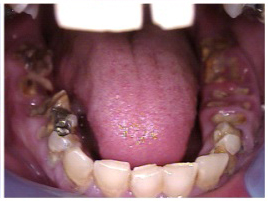

Fig 10. Accumulation of soft plaque is typical of oral hygiene neglect associated with the use of methamphetamine.

Figure 10